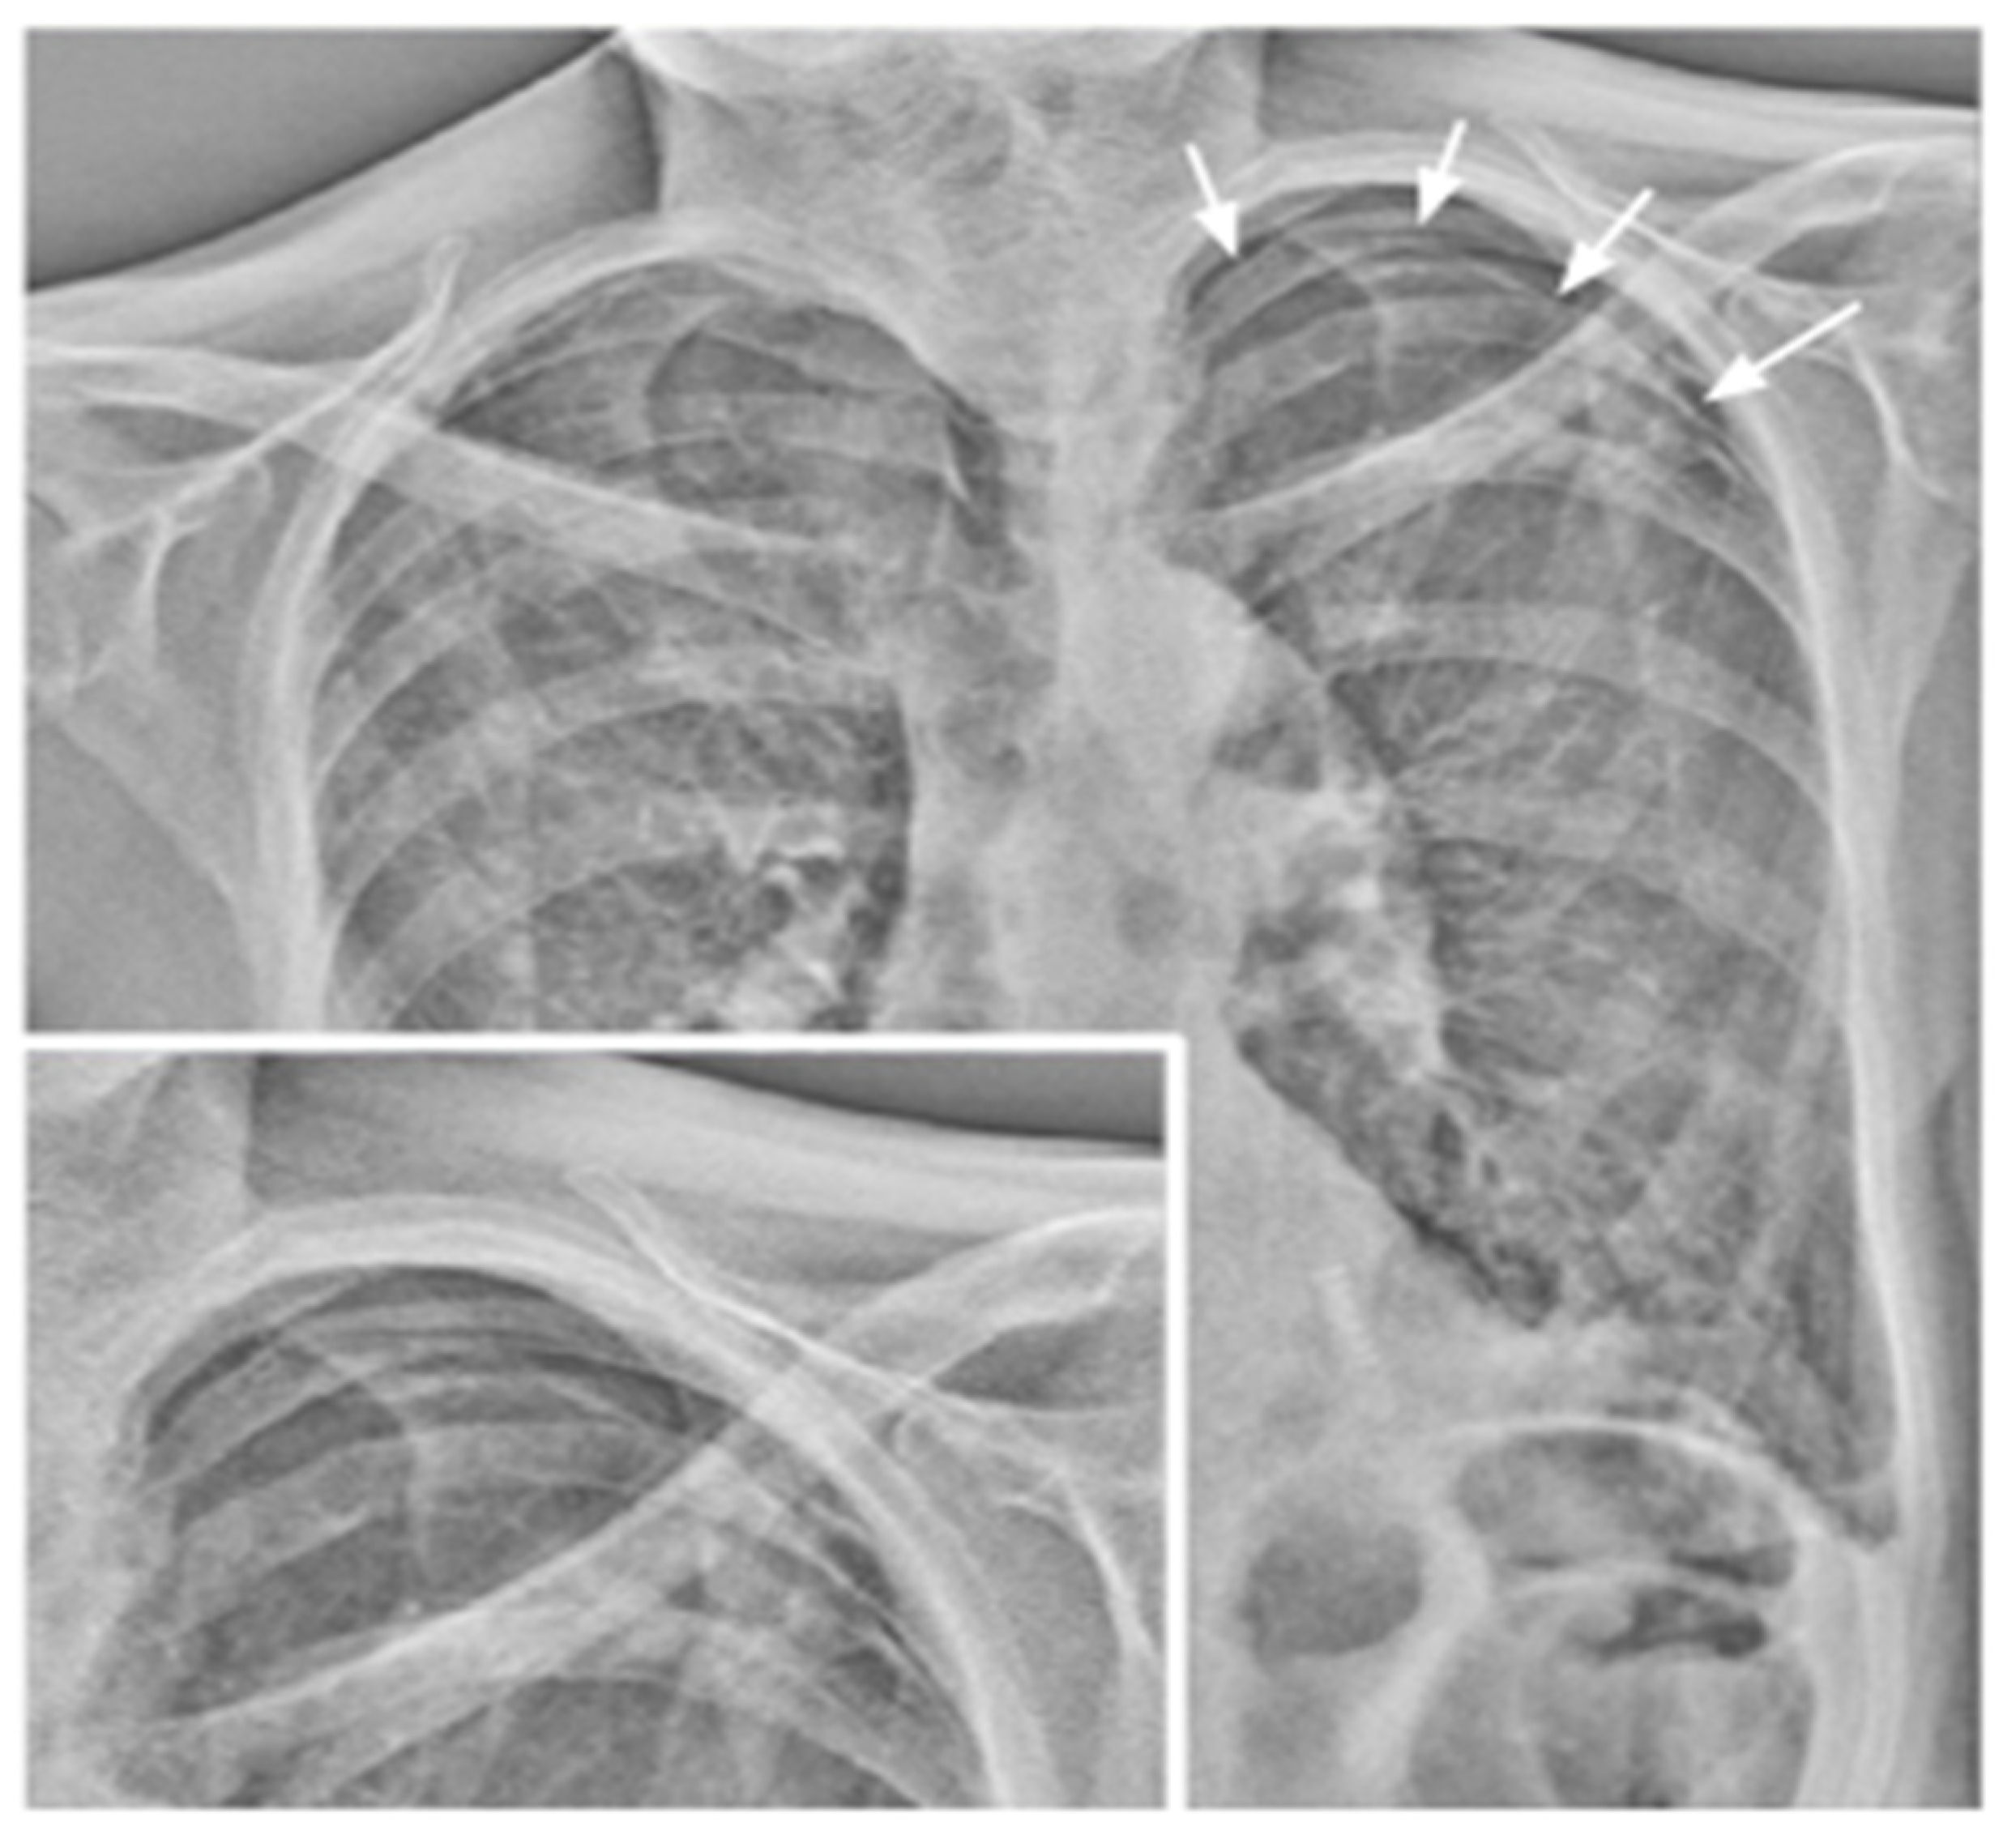

| LM-mode | Vector field representing the movement of different lung areas. | Pixel-by-pixel analysis and tracking in consecutive frames resulting in a two-dimensional vector field. Uses BS-images. | Differential motion analysis of different lung areas; useful for the detection of adhesions and preoperative planning. |

| BS-mode | Bone suppression. | Signal attenuation of costal and clavicular bones within the lung field. Preliminary to LM analysis. | Better visualization of tissues other than bone, with better detection of lung nodules and consolidations. |